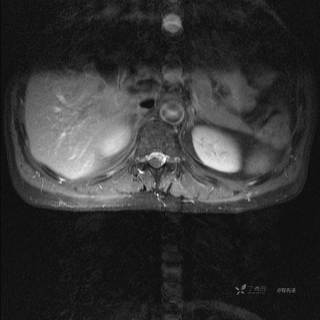

MR

T2

T2压脂

T1

T1增强

T1增强冠状位

T1增强横断位